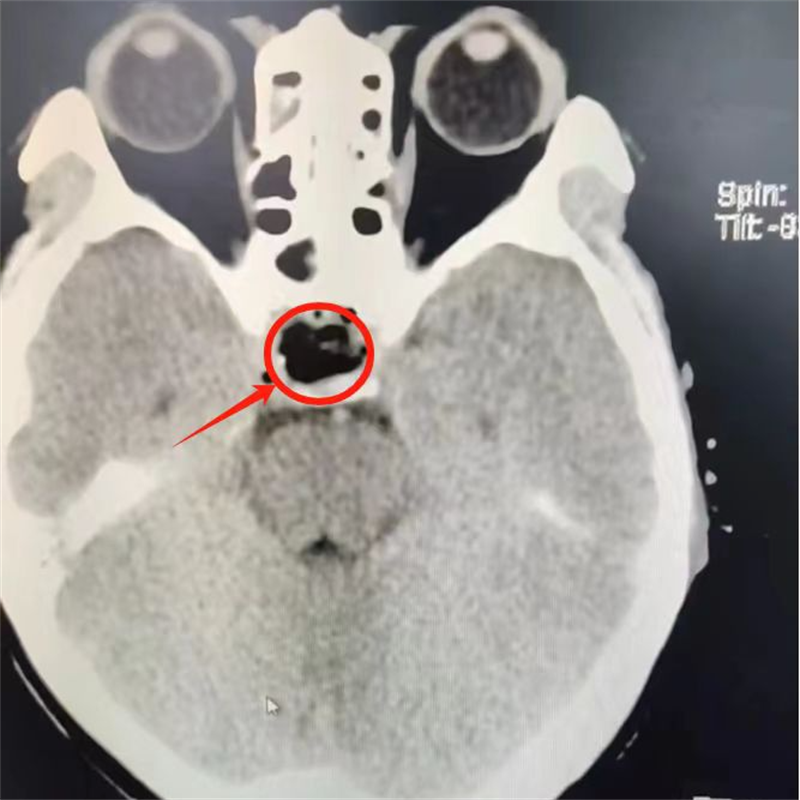

術(shù)前影像

6月13日,手術(shù)實施。經(jīng)驗豐富的神經(jīng)外科內(nèi)鏡團隊、麻醉科通力協(xié)作,利用人體的天然通道——鼻腔作為手術(shù)通道,借助神經(jīng)內(nèi)鏡通過鼻腔里面一個小切口,直達腫瘤部位,進行垂體病灶的微創(chuàng)手術(shù)切除。經(jīng)過近2小時的“奮戰(zhàn)”,腫瘤組織被充分清除,患者無并發(fā)癥,手術(shù)順利完成。術(shù)后復查CT顯示腫瘤全部切除。

6月13日,市中醫(yī)醫(yī)院神經(jīng)外科完成一例垂體瘤微創(chuàng)手術(shù)——內(nèi)鏡下經(jīng)鼻蝶垂體瘤切除術(shù),患者術(shù)后各方面恢復良好,無任何并發(fā)癥,術(shù)后復查顱腦CT顯示腫瘤已完全切除干凈。此次手術(shù)的成功,是該院神經(jīng)外科團隊在神經(jīng)內(nèi)鏡下微創(chuàng)治療腦出血基礎(chǔ)上的進一步技術(shù)提升,標志著市中醫(yī)醫(yī)院腦腫瘤治療進入一個新的微創(chuàng)時代。